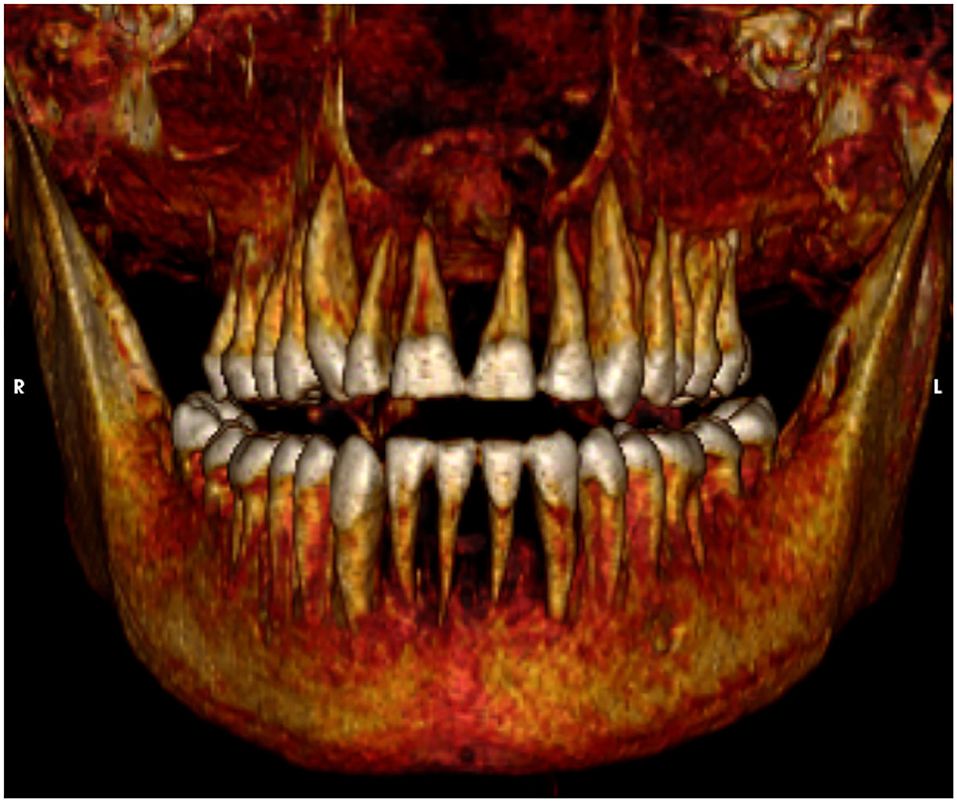

Os exames revelaram que ele tinha cerca de 35 anos quando morreu.

“Amenhotep I parece ter se parecido fisicamente com seu pai: ele tinha um queixo estreito, um nariz pequeno e estreito, cabelo encaracolado e dentes superiores levemente protuberantes”, disse o Dr. Sahar Saleem, o principal autor do estudo, à PA Media.

Os pesquisadores não encontraram evidências de feridas externas ou desfigurações que possam ter contribuído para sua morte.